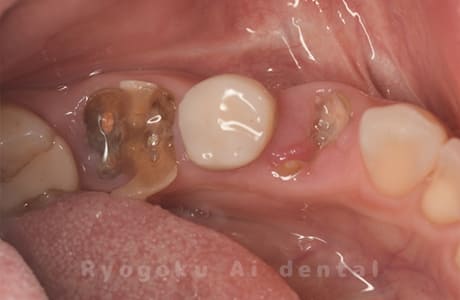

Case12

- 縁下カリエス

- 治療内容

- クラウンレングスニング、ジルコニアクラウン修復

- 治療費用

- 約220,000円

被せ物の中から臭いがするとのことで、被せ物を外したところ大きな虫歯となっていました。このまま被せてしまうと被せ物が外れやすいため、埋まっている歯を出すためのクラウンレングスニング処置を行い、その後、ジルコニアクラウンで被せ物を行いました。